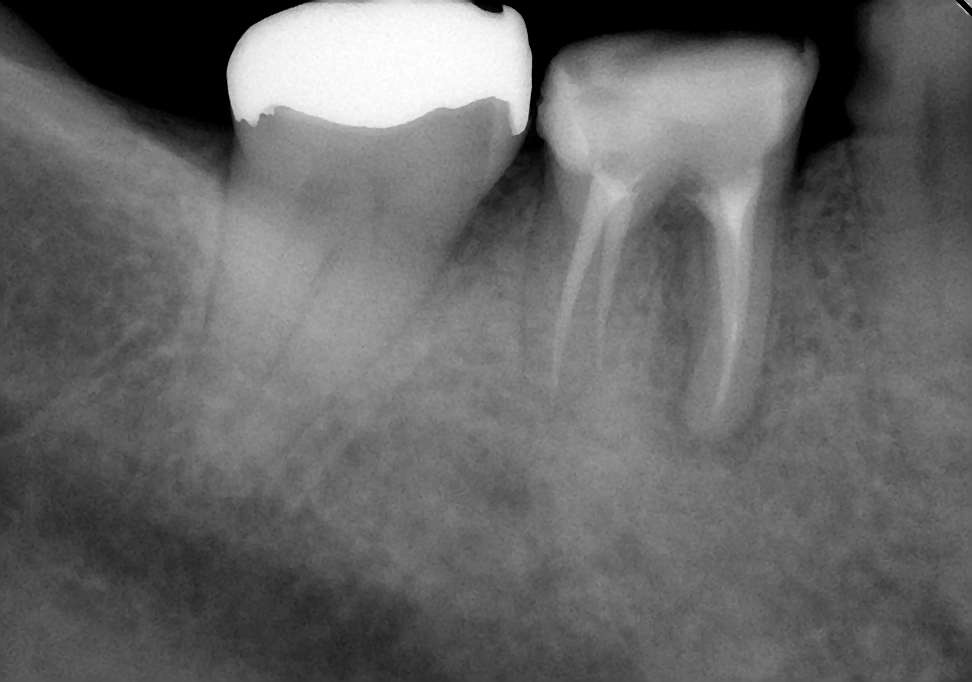

初診時は、時々歯肉から膿が出てきたり、鈍痛を感じることがあったとのこと。レントゲン写真を見ると確かに病気が出来ている影が・・・。さらに、この影の形を見るともしかしたら歯の根が割れているかもしれない。そうなると抜歯に移行しなければなくなる可能性もあることなど病気が治る喜びだけでなく、リスクや起こりうる可能性についても細かく説明させていただいた後に治療を開始しました。

↑初診時